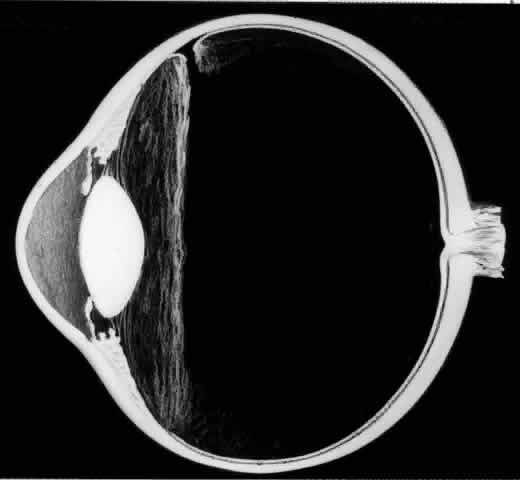

UNFOLDING THE POSTERIOR RETINAL FLAP

One of the most challenging problems in the management of giant retinal tears has been unfolding the inverted posterior retinal flap (Fig. 6). Schepens16 demonstrated that gravity can be used to unfold the flap by placing the patient in the prone position. This led to the development of a multipositional giant tear operating table used to rotate the patient to the prone position during surgery.17,18 Norton and associates19 and Michels20 reported the use of air injection into the vitreous cavity to unfold and tamponade the posterior retinal flap. One of the most important contributions in the management of giant retinal tears with an inverted retinal flap was made by Chang and colleagues,21–24 who demonstrated the value of liquid perfluorocarbons in unfolding the inverted retinal flap. Because this procedure is performed with the patient in the supine position, unfolding of an inverted retinal flap is accomplished more easily and with fewer complications.

Fig. 6. Giant retinal tear with a posterior retinal flap that is inverted over the optic disc. The posterior edge of the giant tear is slightly rolled as a result of epiretinal membrane proliferation. (Freeman HM: Current management of giant retinal breaks and fellow eyes. In Glaser BM, Ryan SJ (eds): Surgical Retina, 2nd ed, pp 2313–2338. St. Louis, CV Mosby, 1994)